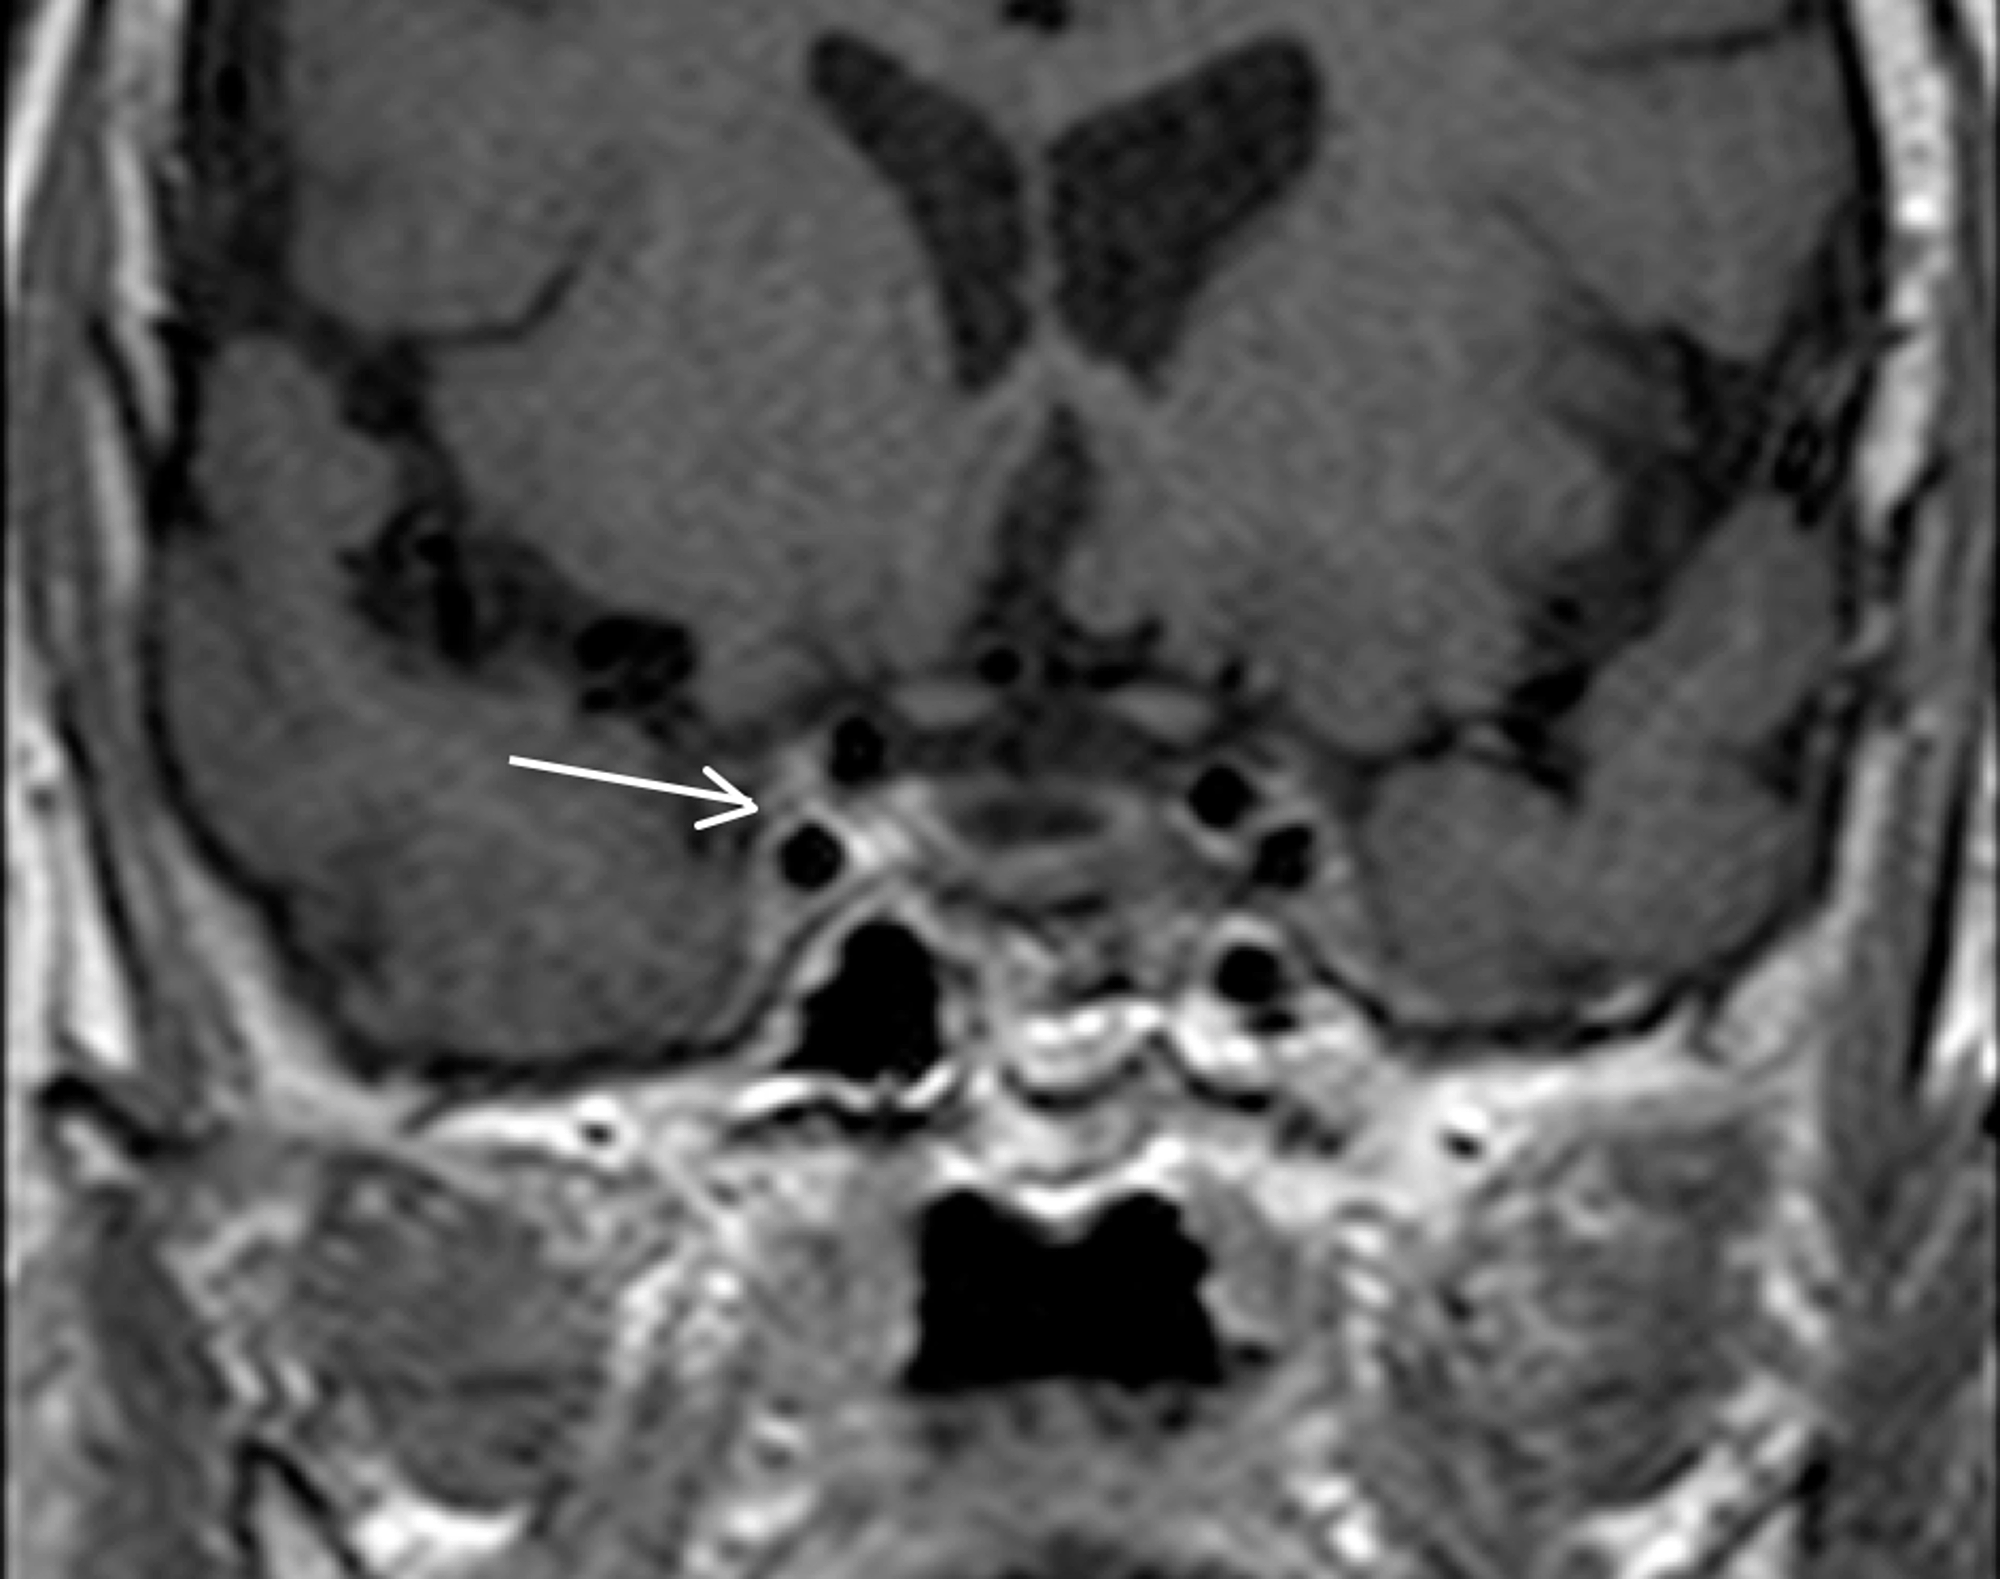

The main complications of orbital cellulitis (Figures 2-4) encountered in our study were:

1. An orbital abscess (Figures 5-6);

2. Preseptal cellulitis and abscess (Figures 7-8);

3. Periorbital cellulitis (Figures 9-10);

4. Dacryoadenitis (Figures 11-12);

5. Optic neuritis/perineuritis (Figure 13);

6. Cavernous sinus thrombophlebitis and thrombosis (Figure 14).

The most common complication of orbital cellulitis was orbital/periorbital abscess formation (eight cases, 53.3%), followed by optic neuritis (four cases, 26.67%), intracranial involvement (four cases, 26.67%), dacryoadenitis (three cases, 20%) and cavernous sinus thrombophlebitis (three cases, 20%).